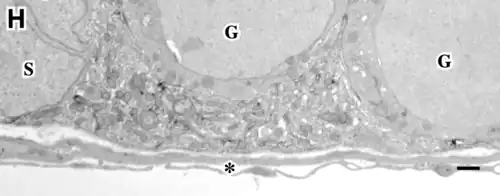

Los túbulos presentan dos compartimentos clásicos: uno basal y otro luminal (o adluminal). Ambos presentan características anatómicas y funcionales diferenciales.[9][10][8][6]

Compartimento basal del túbulo seminífero

Es el área definida entre la lámina basal del túbulo y las uniones estrechas (thigth junctions en inglés), de las células de Sertoli.

- Consta de: una capa de células mioides contráctiles peritubulares, una lámina basal y principalmente de las células de Sertoli. Estas últimas rodean completamente con sus prolongaciones citoplasmáticas a las células germinales y están adheridas entre sí por uniones estrechas en sus membranas.[11]